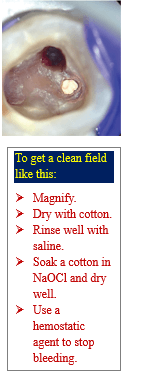

- Stop drilling immediately if you see unusual bleeding.

- Optional inspect visually using magnification (dental microscope or 3.5 X loupes).

- Dry the area gently with sterile cotton pellets to locate the perforation site.

- Gently irrigate using:

- 2.5–5.25% sodium hypochlorite (NaOCl) for disinfection.

- Saline or sterile water to rinse residual NaOCl

- Avoid pressure irrigation to prevent naocl extrusion.

- Apply light pressure with a sterile cotton pellet or a paperpoint soaked in:

- 1:1000 epinephrine for hemostasis

- Wait 1–3 minutes to see if bleeding stops.

- Persistent bleeding indicates possible larger injury (large perforation).